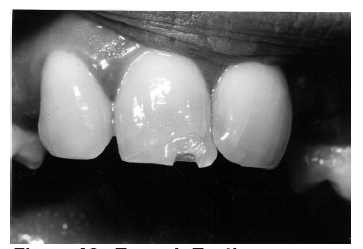

Macrodontia is the formation of unusually large teeth. Most commonly, this developmental anomaly presents as a single enlarged tooth, and, less frequently, as multiple macrodonts. Figure 29 is a right maxillary lateral incisor macrodont with a small hypoelastic enamel defect on the labial tooth surface.

The patient’s radiographic image, shown in Figure 30 clearly outlines the macrodont and additionally reveals an impacted maxillary canine.

Figure 29 - Maxillary Right Lateral Incisor Macrodont

Figure 29

Figure 30 - Macrodont and Impacted Canine

Figure 30